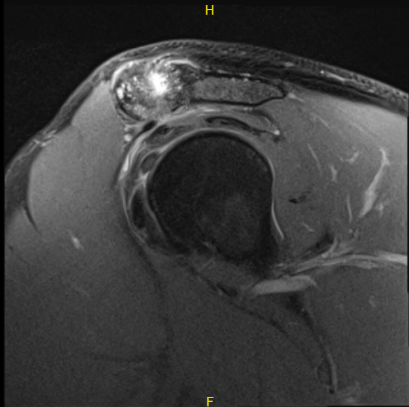

The patient presented an MRI result that showed high-grade partial-thickness articular surface tear at the supraspinatus tendon insertion. Low-grade partial-thickness articular surface tear of the distal infraspinatus tendon. Moderate AC joint arthrosis.

A small subacromial spur predisposes the patient to external impingement. Nondisplaced tear of the posterosuperior labrum. Mild subacromial subdeltoid bursitis.